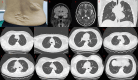

Tuberous sclerosis complex (TSC) is an autosomal dominant genetic disorder characterized by the development of benign tumors and lesions in multiple organ systems. The syndrome arises from heterozygous mutations in either TSC1 or TSC2. In this study, we identified a family with a TSC1 c.363 + 668G > C mutation exhibiting diverse clinical phenotypes. The proband and affected family members exhibited multifocal nodular pneumocyte hyperplasia (MMPH), renal hamartomas, bone marrow hyperplasia, and pulmonary lymphangioleiomyomatosis (LAM), with genetic co-segregation analysis confirming the association between the mutation and the clinical phenotype. Genetic co-segregation analysis demonstrated that the TSC1 c.363 + 668G > C mutation was consistently associated with the observed clinical features in this family. Using first-generation Sanger sequencing, we identified a heterozygous splicing variation located in intron 5 of TSC1 (NM_000368.5). In vitro cell and family Minigene results show that TSC1 c.363 + 668G > C mutation can lead to abnormal retention of 92 bp intron sequence in different positions, which may be related to the alternative splicing phenomenon that the same gene produces different splicing variants in different tissues or development stages. The 3D protein structure analysis using Chimera revealed that the mutation site was located at the 363rd base, within the intron between the 121st and 122nd amino acids. This mutation resulted in the insertion of a 92-base sequence, causing a frameshift that led to premature termination of the TSC1 protein after the translation of 26 amino acids. Additionally, the 121st amino acid was altered from lysine to asparagine, significantly shortening the mutated TSC1 protein. These findings provide critical experimental evidence supporting the potential pathogenic mechanism of the TSC1 c.363 + 668G > C mutation. Future research should focus on validating this splicing abnormality in patient-derived cells or tissues and investigating its impact on protein expression and functional activity to better understand its role in disease progression.Clinical trial number: K2024-09-144.